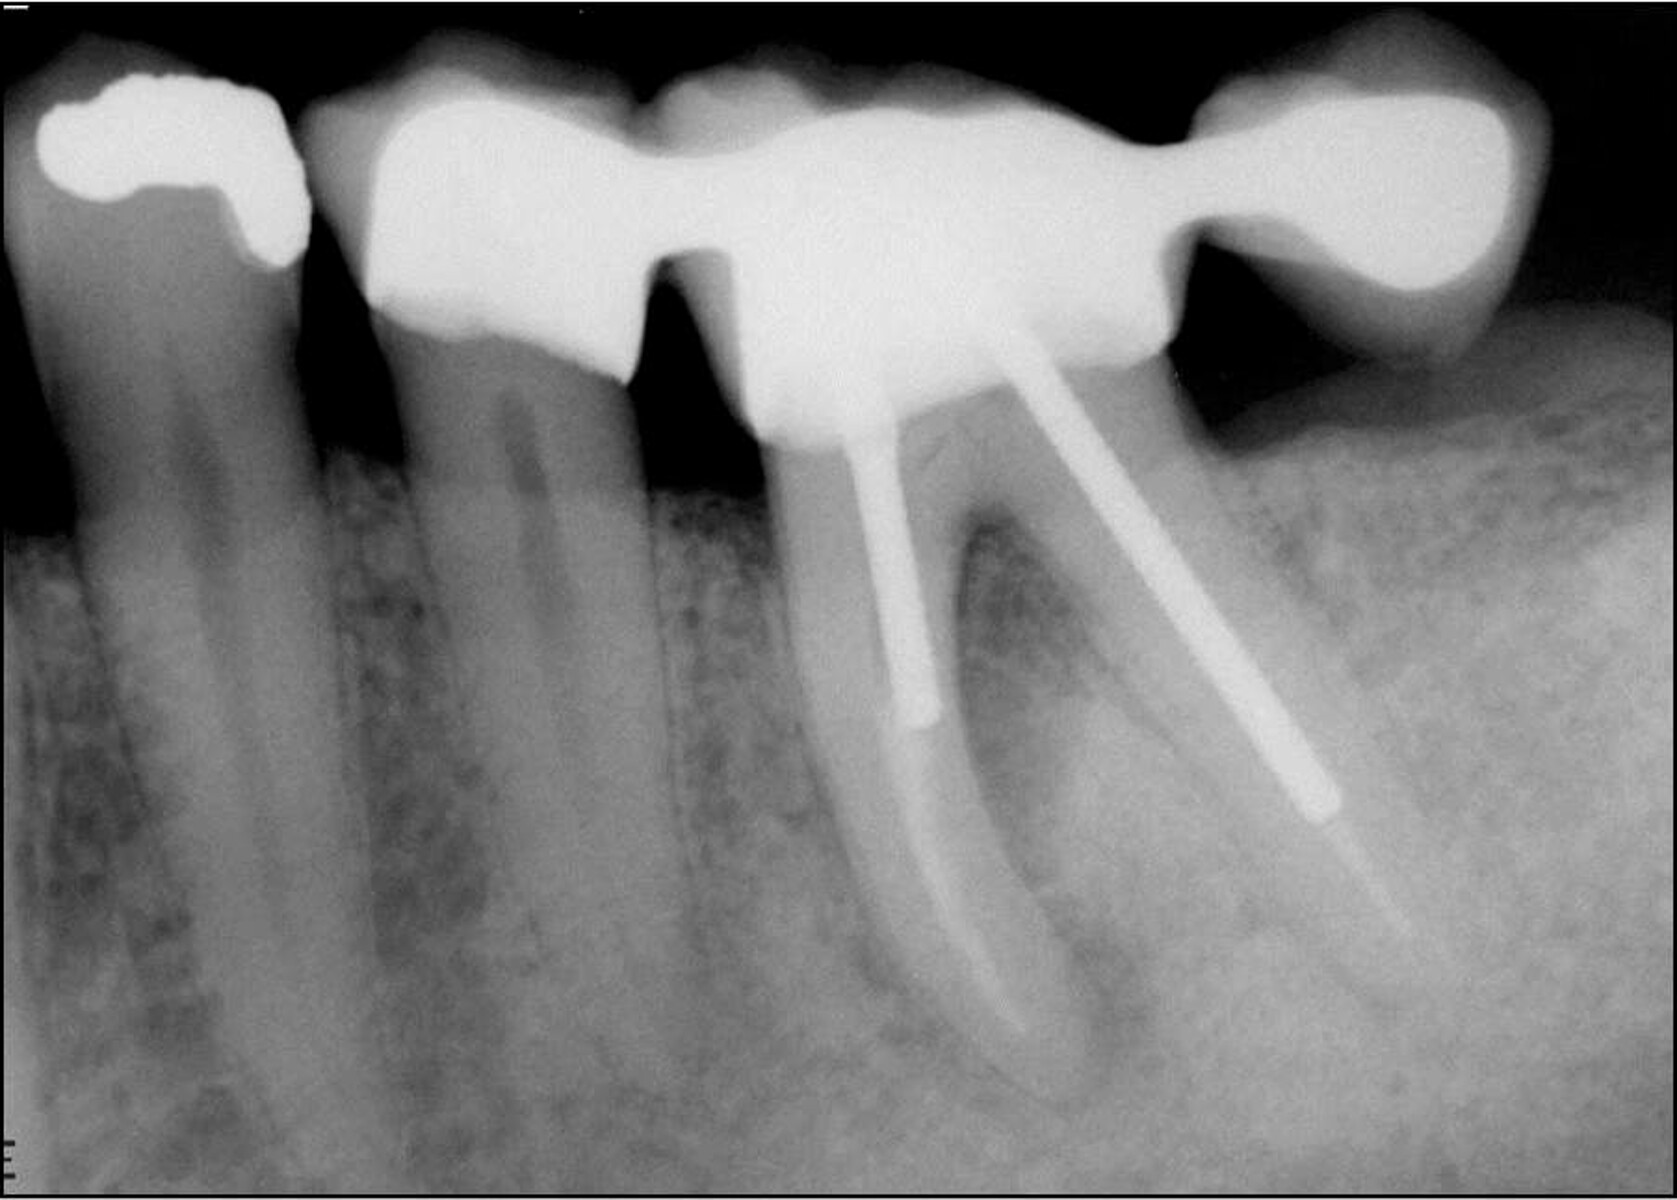

root canal cases Bifurcated Root  Find out the causes, symptoms, diagnosis and prognosis of furcation involvement of a dental infection. This chapter reviews the external and internal morphology of roots and canals, and introduces a new coding system for classifying. A bifurcation is a juncture of two roots at the base of a tooth, which can be affected by bone loss and periodontal disease. Mandibular. Bifurcated Root.

(PDF) Endodontic Treatment of Bifurcated Root Canal in Mandibular Bifurcated Root  The mandibular first and second premolars typically present with single roots but may have bifurcated roots in rare situations. Mandibular first premolars may also exhibit a bifurcated root, one buccal, and one lingual (fig. Learn what bifurcation and trifurcation are in a tooth, how they affect the root structure and the surrounding bone, and how to treat them. Which of. Bifurcated Root.

Vertical Root Fracture in Buccal Roots of Bifurcated Maxillary Bifurcated Root  Find out the causes, symptoms, diagnosis and prognosis of furcation involvement of a dental infection. This chapter reviews the external and internal morphology of roots and canals, and introduces a new coding system for classifying. Mandibular first premolars may also exhibit a bifurcated root, one buccal, and one lingual (fig. Learn what bifurcation and trifurcation are in a tooth, how. Bifurcated Root.

Cureus Endodontic Management of Maxillary Central Incisor with Rare Bifurcated Root  Mandibular first premolars may also exhibit a bifurcated root, one buccal, and one lingual (fig. Which of the following premolar teeth normally has a bifurcated root? The mandibular first and second premolars typically present with single roots but may have bifurcated roots in rare situations. Find out the causes, symptoms, diagnosis and prognosis of furcation involvement of a dental infection.. Bifurcated Root.